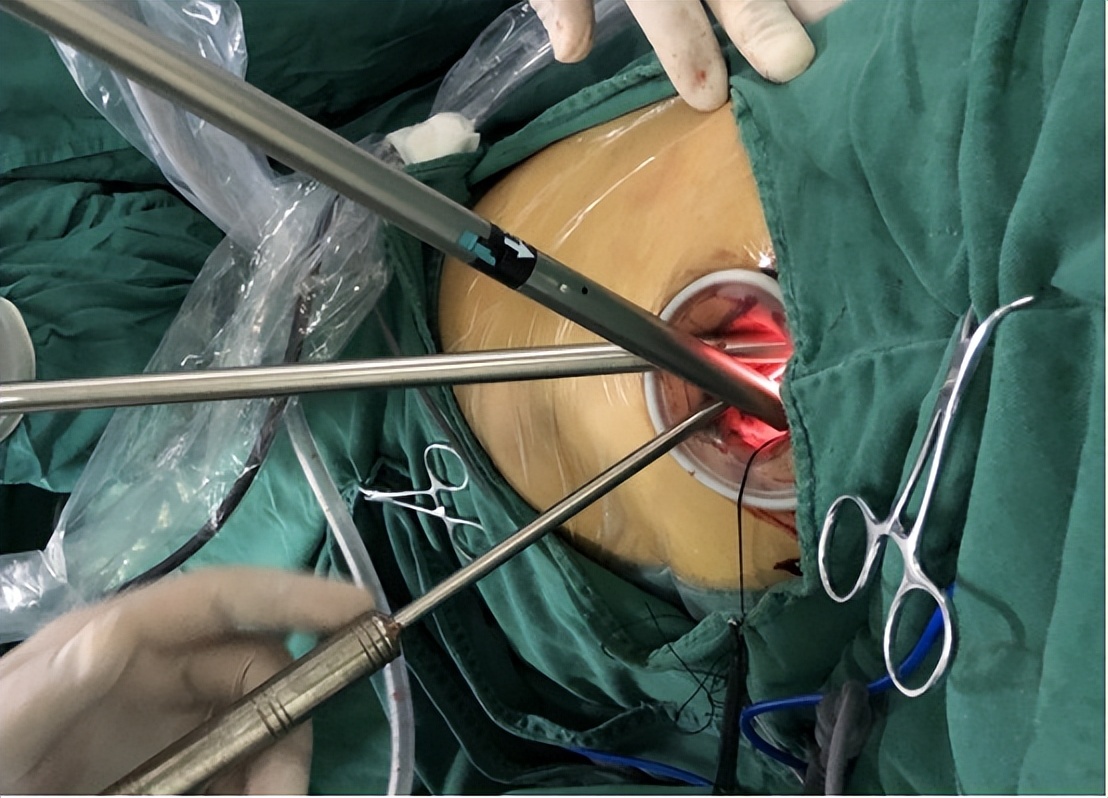

五、活检位置与术后

我们的研究表明并发症没有明显的增加。在支气管镜下冷冻肺活检中,主要并发症为出血、气胸、纵隔肺炎。在我们的研究中,出血均为轻微渗出,不用额外的干预即可停止,术后也没有引流出持续性血胸水的情况。

一方面,可能因为在冷冻时术口周围血管收缩达到了止血的目的。另一方面,我们在操作时,也采取了一些减少出血风险的措施。

例如在观察到病变情况无明显差别的情况下,活检部位尽量选择肋骨上,以避免损伤肋骨下面的神经维管束,同时控制住冷冻的时间,时间延长,会撕裂更大、更深的组织。

然而出血的风险也更大,同时注意防止过度*力暴**拽拉。虽然活检深度更深,但是没有明显增加疼痛、胸膜反应的情况,考虑与冷冻的止痛作用有关。

在我们一个结核性胸膜炎病例中,患者多发胸膜结节,用冷冻活检可以取下完整的结节,而常规钳则无法做到。

在另一病例中,胸膜表面分泌物过于松软,用常规钳几乎无法钳取,因为分泌物含水量多,可以使用冷冻活检取*体下**积大的标本,这也从理论上证明冷冻活检可以获得更深度的活检、挤压伪影更少。

我们在本研究试验组所有患者中均成功取到了胸膜组织,从而证明了内科胸腔镜下胸膜冷冻活检作为胸膜活检新的辅助技术的可行性。尽管诊断率没有明显的差异。

暂时没有关于胸膜冷冻活检的技术操作规范,但是根据我们的经验,冷冻活检在技术上很容易操作,术者在手术过程中没有感到明显的难度。

另外冷冻活检钳也很适用于内科胸腔镜操作通道,而且也能在切线方向上进行活检。基于以上观点,冷冻活检在目前的胸膜活检中不是必要的。